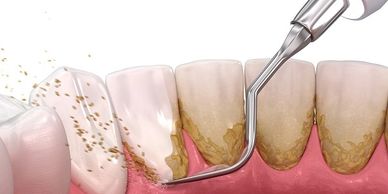

In the image in this section you will see an instrument. This is called a periodontal probe. The hygienist uses this instrument to measure the space between your tooth and the gum, this is called the pocket. You will hear about your pockets at every visit. It's best to understand what they are. Each periodontal probe has a set of markings on it. These measurements indicate one millimeter (mm). A healthy gum pocket is between 1 and 3 mm. If the gums are inflamed (gingivitis), the pocket will read 4 mm. This is a warning that your gums are unhappy. If the probe reads a measurement 5 to 6 mm this is active periodontal disease, it is best to catch periodontal disease during this stage. If a probe reading is beyond 6 mm, there may be a serious periodontal infection that requires a specialist. A periodontist, is a dental specialist that treats moderate to severe periodontal disease, surgical intervention may be necessary at this point.

If during your initial visit, or annual assessment, your pockets are getting deeper a deep cleaning may be needed. Hygienist and dentists routinely recommended scaling and root planing (SRP), a non-surgical treatment, used to remove plaque (biofilm) and calculus (tarter build-up).

Remember -- this is very important -- bacteria causes periodontal disease. Period. Repeat: bacteria (found in plaque biofilm) causes periodontal disease and the destruction of your periodontium (supporting structures). Bacteria in conjunction with host response determines disease progression.

I usually start with the ultrasonic or Cavitron. This is the "electric" cleaner the hygienist uses on your teeth to clean plaque and calculus. Now, most patients can tolerate this procedure just fine, but I know there are some that cannot. If you cannot tolerate the electric cleaners, just let us know. Your hygienist can skip it, or if needed, use local anesthetics/desensitizers to help.

Next, the hygienist will use a series of hand instruments to remove residual plaque and/or calculus. This is commonly referred to as the "scraping" portion of your cleaning. This is important! Once all plaque and calculus has been removed, a prophy cup polish and floss will finish it up.